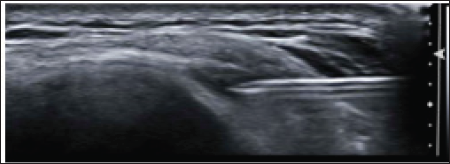

Our institution examined cases of patients who presented with both anterolateral parameniscal cysts together with Iliotibial Band Syndrome. We used ultrasound to confirm the diagnosis of parameniscal cysts and provide guidance for aspiration and injection of a steroid-anesthetic mixture. Operators performed scans with an 18-5 MHz linear transducer and an 11-3 MHz Resona 7 (Mindary Healthcare) linear transducer, on an Acuson S3000 scanner (Siemens Healthcare). Patients were positioned on their side or supine, with the hip in neutral flexion and the knee at 30° to 45° degrees of flexion. To begin, the transducer was placed over the anterior knee on the long axis to the patellar tendon. We then scanned laterally and first identified the iliotibial band in the long axis of the coronal plane. We followed the iliotibial band from above the lateral femoral condyle to its insertion on Gerdy's tubercle, located on the proximal lateral tibia (Figure 4). Of note, the iliotibial band is separated from the lateral margin of the knee by the lateral synovia recess and the ITB bursa. The lateral synovial recess is a layer of richly innervated and vascularized adipose tissue deep to the ITB.

Figure 4: We followed the iliotibial band from above the lateral femoral condyle to its insertion on Gerdy's tubercle, located on the proximal lateral tibia.

Figure 5: The same needle is then advanced under direct ultrasound guidance into the parameniscal cyst along the anterolateral margin of the lateral meniscus

The ITB bursa is an adventitial bursal extension from the synovial capsule. When identifying the ITB bursa between the ITB and lateral femoral condyle, it is important to evaluate the tissues between the iliotibial tract and the distal femur more proximally for disorders related to ITBS. The anterior horn of the lateral meniscus is deep in the iliotibial tract. Following identification of the paramenical cysts, researches injected an anesthetic corticosteroid mixture of 1 mL (40 mg/mL) of triamcinolone (Kenalog; Apothecon, Bristol-Myers Squibb Co, Princeton, NJ), 0.5 mL of 1% lidocaine, and 0.5 mL of 0.5% bupivacaine (Sensorcaine; AstraZeneca Pharmaceuticals, Wilmington, DE). Anesthesia of patients' skin was achieved with injection of 1 mL of 1% lidocaine through a 25-gauge, 1.5-in hypodermic needle using a sterile technique. The same needle is then advanced under direct ultrasound guidance into the parameniscal cyst along the anterolateral margin of the lateral meniscus (Figure 5). Then, another 25-gauge needle was placed into the undersurface of the adjacent ITB. Once the both needles were in the correct position, the therapeutic mixture was injected. Distention of the bursae was the determining factor for a successful injection.